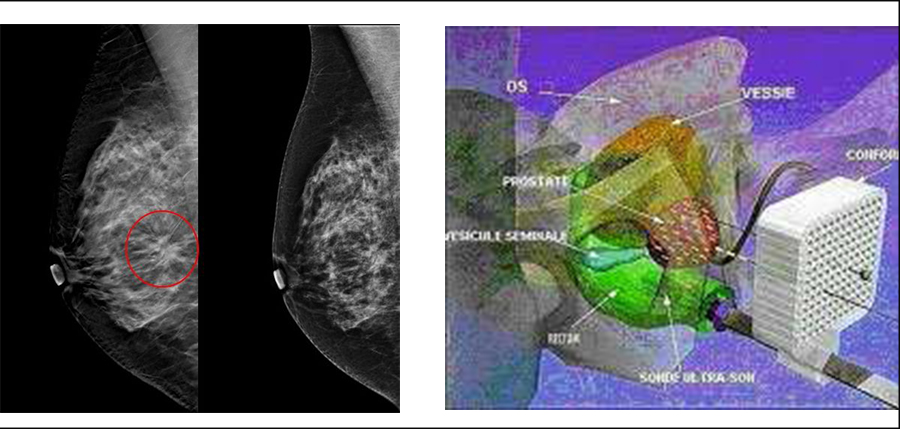

Les innovation Diagnostiques et Thérapeutiques dans le cancer du sein et de la Prostate

Dans le cadre de la formation continue post-universitaire, le Centre d'Oncologie AL AZHAR de Rabat, organise une Table Ronde le 18 Avril 2017 à l'Amphitrite Skhirat sur les actualités dans les Cancers du sein métastatiques en 2017,les pièges de la mammographie,la curiethérapie dans le cancer de la prostate ainsi que l'étude de Cas cliniques pratiques.